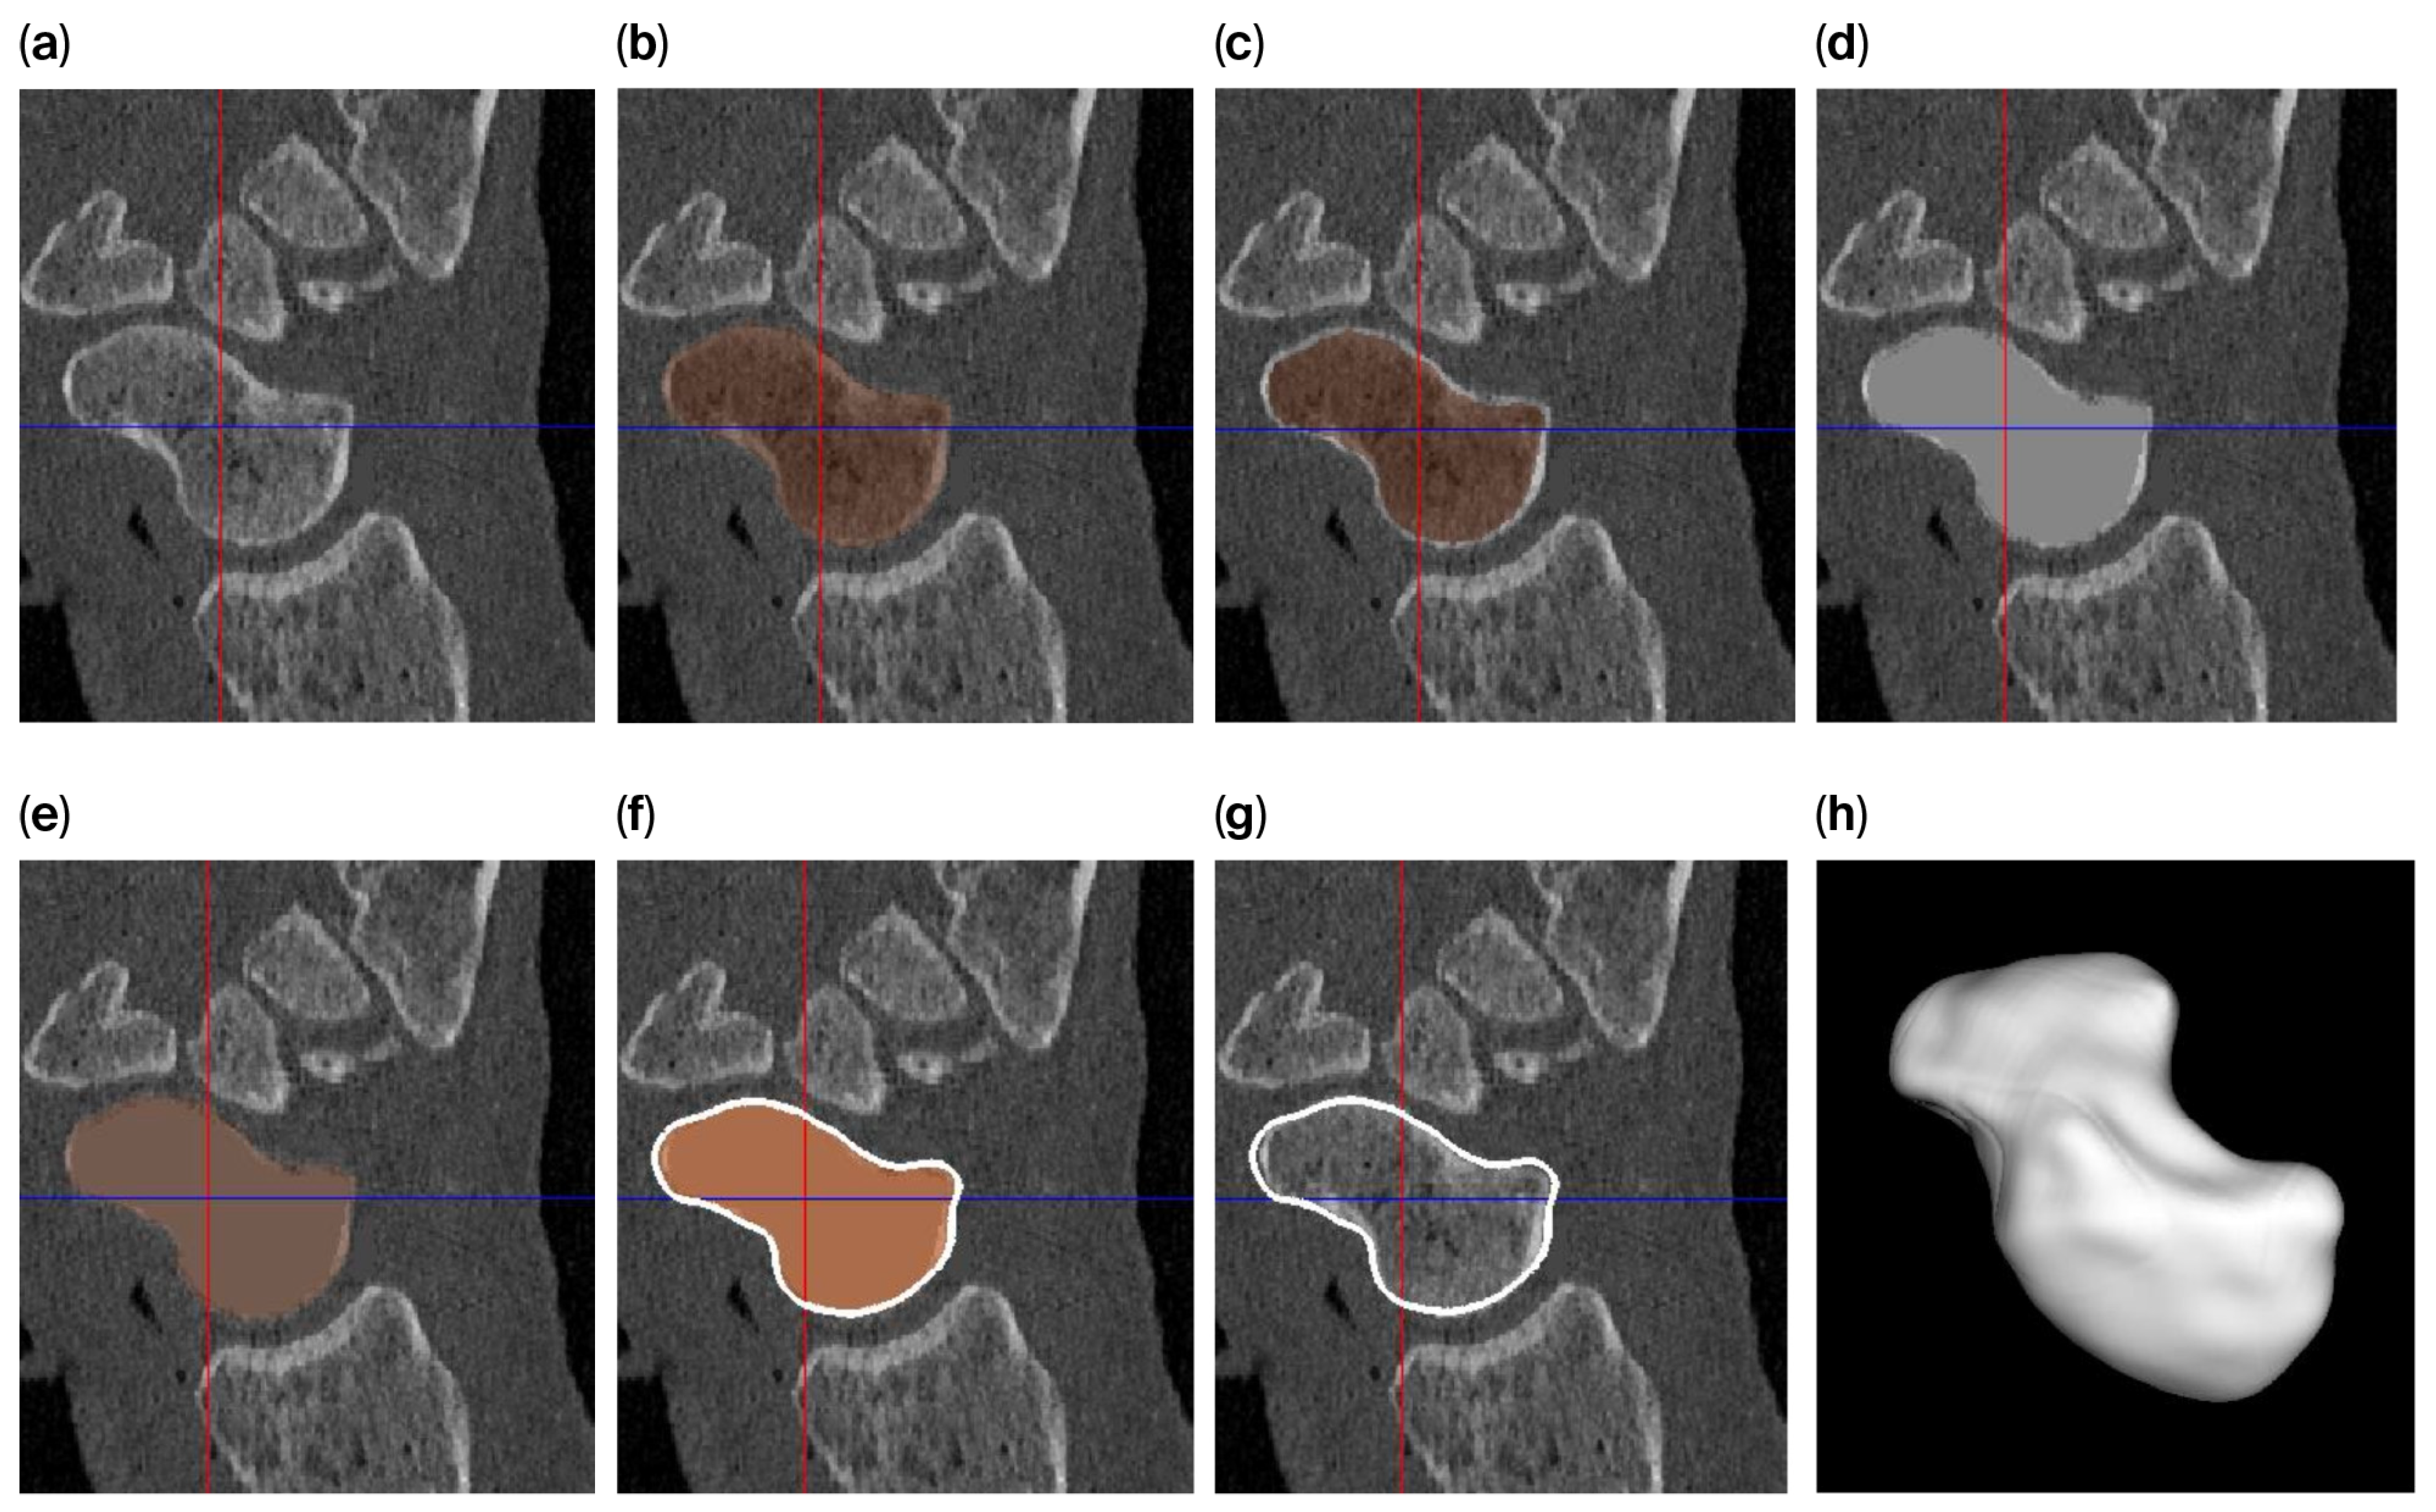

The level-set algorithm initially uses Gaussian smoothing to remove these irregularities, but applying such a smoothing filter to a thin cortical boundary may cause this layer to widen (caused by the point-spread function of the Gaussian filter kernel), which in turn causes the scaphoid object to become slightly enlarged after segmentation. Therefore, different segmentation approaches are used to answer the research questions (Figure 2) as follows:

• For investigating the size difference and reproducibility of segmentation between frozen and thawed conditions, image smoothing was carried out with rather limited parameters (σ = 0.3 mm; level-set iterations = 20), resulting in a tight-fitting segmentation.

• To achieve a smooth scaphoid object for implantation, further image smoothing was used (σ = 1.0 mm; level-set iterations = 30), resulting in a segmentation with a smooth outline. However, for the reasons outlined above, the object will become slightly enlarged. To circumvent this issue, we first changed the underlying gray-level image so that the cortical layer is no longer thin. This was achieved by first segmenting the scaphoid by region-growing and region-filling conditions (no level set) and subsequently eroding the segmented object by 0.5 mm. The masked (trabecular bone) region was subsequently replaced by a CT value of 2106 HU (an approximate intensity value of the cortical layer). As a result, the thin layer disappears, minimizing the widening effect. This adapted gray-level image was subsequently segmented as normal, as described above (σ = 1.0 mm; level-set iterations = 30).

Figure 2. Segmentation process for a smooth 3D model of the scaphoid: (a) original image; (b) segmentation using region growing and filling; (c) after 0.5 mm of erosion; (d) after filling the segmented part of the gray-level image with a value of 2106 (the approx. value of the cortical layer); (e) after region growing and filling of the modified image; (f) polygon outline; (g) slight mismatch between the outline and the underlying gray-level image; and (h) a smooth 3D representation of the scaphoid polygon.